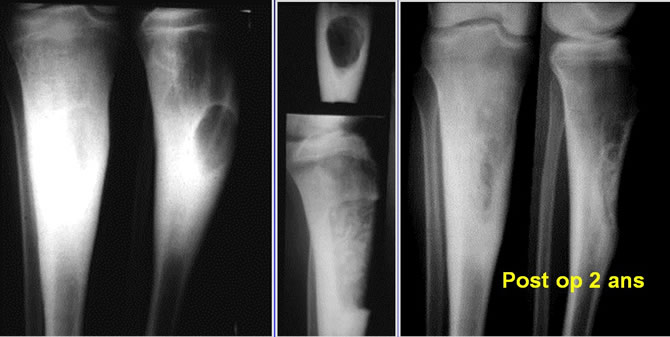

Dégénérescence d'une exostose fémorale

Malade de 42 ans, exostose ancienne peu symptomatique jusqu'il y a 2 mois.

Depuis douleurs et tuméfaction croissante.

Exérèse large d'emblée confirmant la dégénérescence.

Dégénérescence d'une exostose tibiale

Malade de 26 ans ayant remarqué depuis 4 mois une tuméfaction peu douloureuse progressivement croissante du genou.